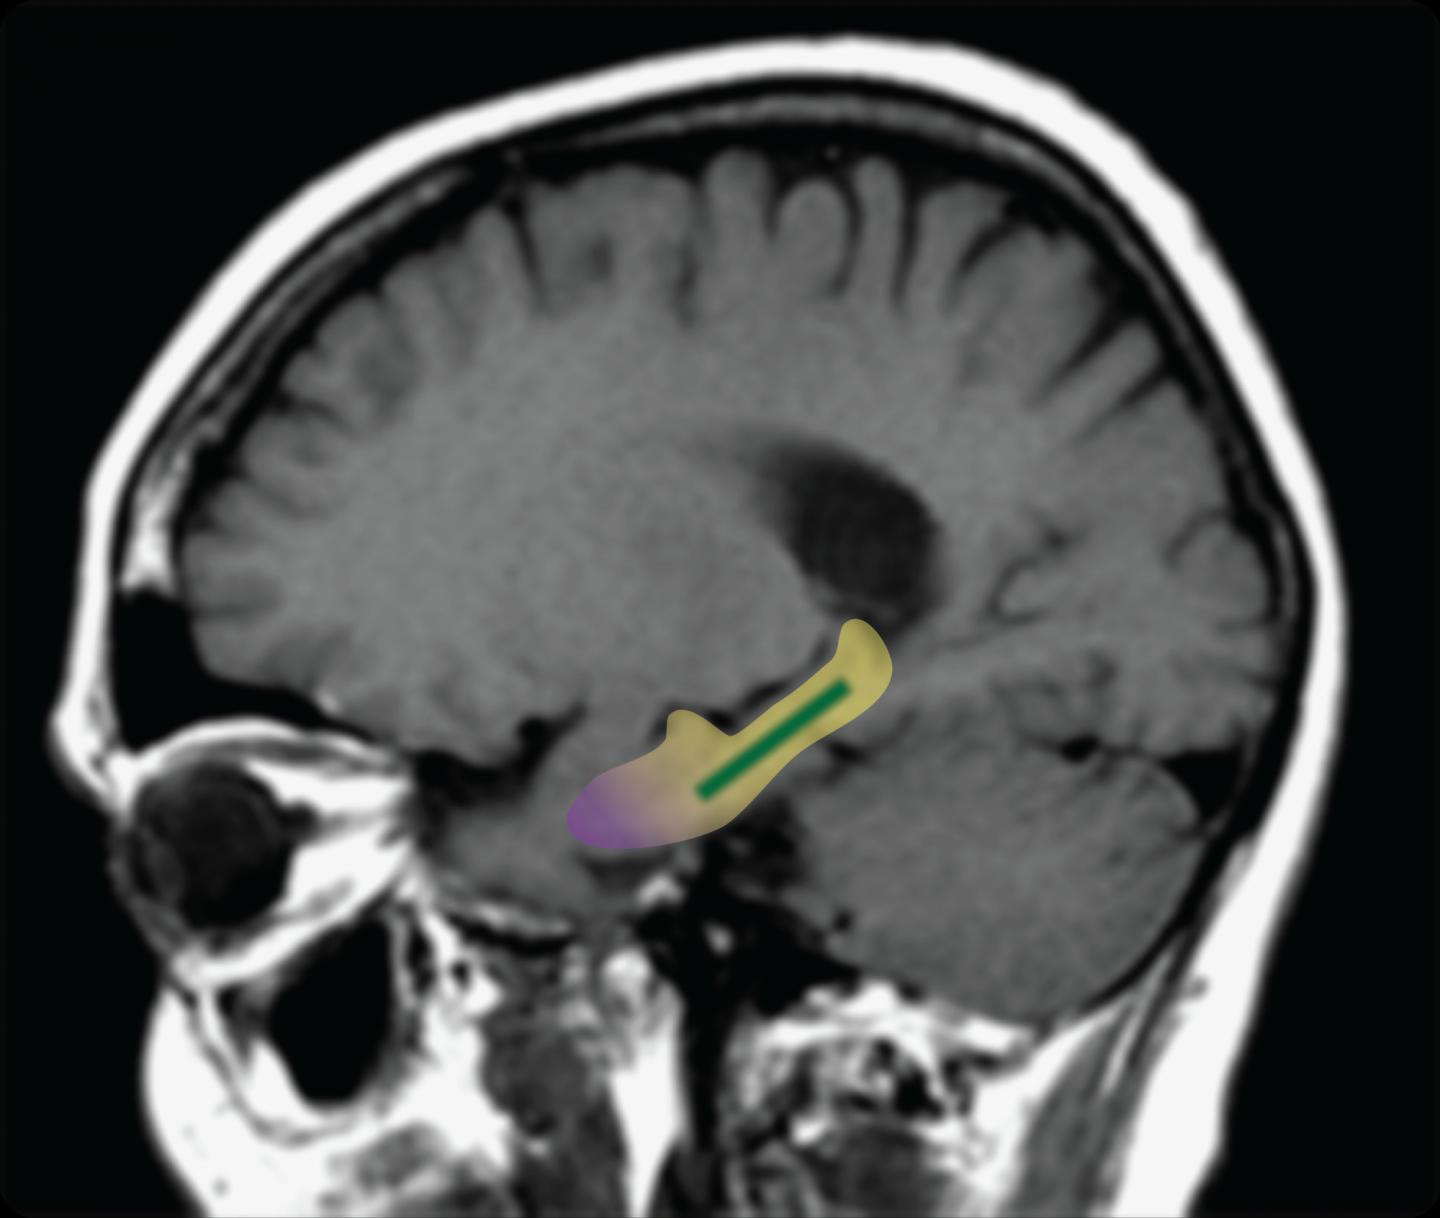

Previous work, including by the laboratory of senior author Scott A. Small, MD, had shown that changes in a specific part of the brain—the dentate gyrus—are associated with age-related memory decline. Until now, however, the evidence in humans showed only a correlational link, not a causal one. To see if the dentate gyrus is the source of age-related memory decline in humans, Dr. Small and his colleagues tested whether compounds called cocoa flavanols can improve the function of this brain region and improve memory. Flavanols extracted from cocoa beans had previously been found to improve neuronal connections in the dentate gyrus of mice.

In the CUMC study, 37 healthy volunteers, ages 50 to 69, were randomized to receive either a high-flavanol diet (900 mg of flavanols a day) or a low-flavanol diet (10 mg of flavanols a day) for three months. Brain imaging and memory tests were administered to each participant before and after the study. The brain imaging measured blood volume in the dentate gyrus, a measure of metabolism, and the memory test involved a 20-minute pattern-recognition exercise designed to evaluate a type of memory controlled by the dentate gyrus.

"When we imaged our research subjects' brains, we found noticeable improvements in the function of the dentate gyrus in those who consumed the high-cocoa-flavanol drink," said lead author Adam M. Brickman, PhD, associate professor of neuropsychology at the Taub Institute.

Two innovations by the investigators made the study possible. One was a new information-processing tool that allows the imaging data to be presented in a single, three-dimensional snapshot, rather than in numerous individual slices. The tool was developed in Dr. Small's lab by Usman A. Khan, an MD-PhD student in the lab, and Frank A. Provenzano, a biomedical engineering graduate student at Columbia. The other innovation was a modification to a classic neuropsychological test, allowing the researchers to evaluate memory function specifically localized to the dentate gyrus. The revised test was developed by Drs. Brickman and Small.